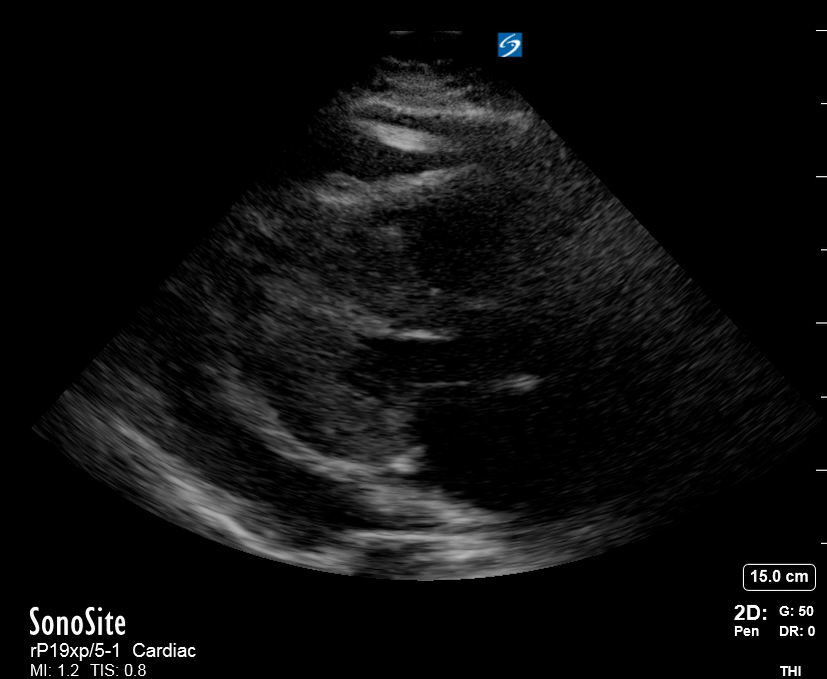

THE VIEWS

The PLAX view is versatile and allows the recognition of multiple landmarks, making it good for visual estimation of LV contractility. It is essential to optimize the view ensuring a true sagittal long axis, as being oblique to the LV chamber may underestimate its size and overestimate its emptying. The PSAX view at the level of the papillary muscles reveals the entire muscular circumference and concentric squeeze of the LV. It is useful to estimate both global function and focal wall motion abnormalities. The A4C view, although technically challenging, provides good insight into the global myocardial function and chamber size.

LV CONTRACTILITY

Qualitative assessment of the LV and visual estimation of Ejection Fraction is based on three parameters:

Endocardial excursion.

Myocardial thickening.

Movement of the anterior leaflet of the mitral valve.

A qualitative assessment is typically categorised as:

Normal (LVEF 50-65%)

Moderately Depressed (LVEF 30-50%)

Severely Depressed (LVEF < 30%)

Hyperdynamic (LVEF > 65%)